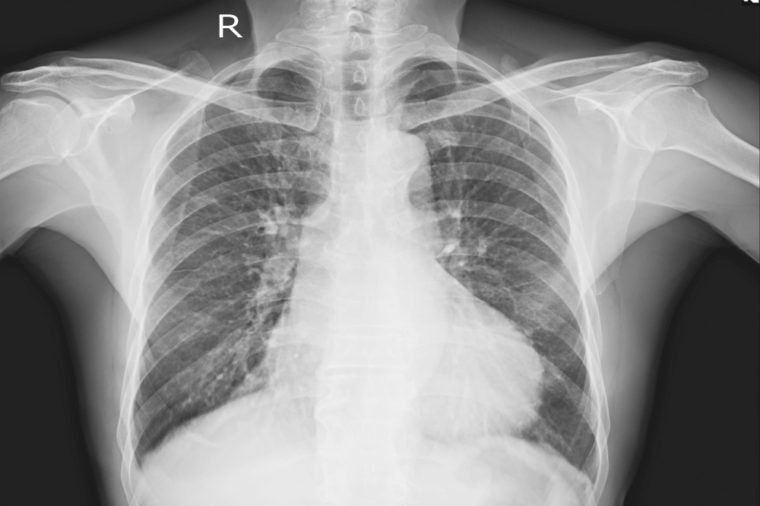

Cancer

Another source of shoulder pain could also be cancer—most often, lung cancer. According to a 2015 study, 14 percent of people with mesothelioma (which is usually due to asbestos exposure) reported shoulder pain, and it was often the first symptom. A couple of other types of lung cancer may also cause shoulder pain: pancoast tumors, which are located in the upper lungs, and metastatic lung cancer. The tricky thing about lung-cancer–related shoulder pain—called “referred pain” because it starts elsewhere in the body—is that it may not be severe and it can be mistaken for arthritis. Other telltale signs that cancer is the cause can be a chronic cough that sometimes produces blood, labored breathing, fatigue, unexplained weight loss, and recurrent respiratory infections.